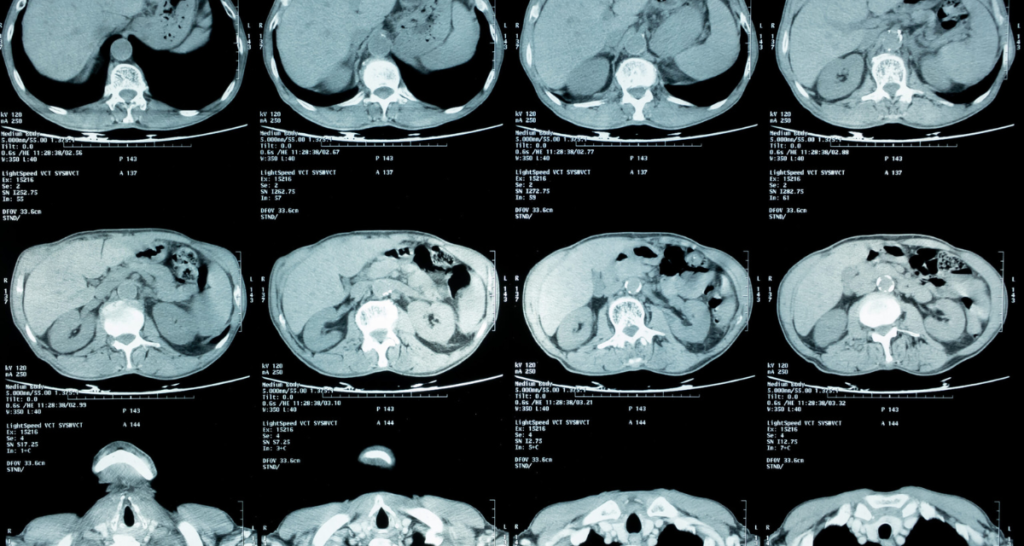

Abdominal or Pelvic MRI

These scans evaluate organs such as the liver, kidneys, uterus, prostate, and bowel. Reports may mention cysts or small benign findings that are common and harmless.